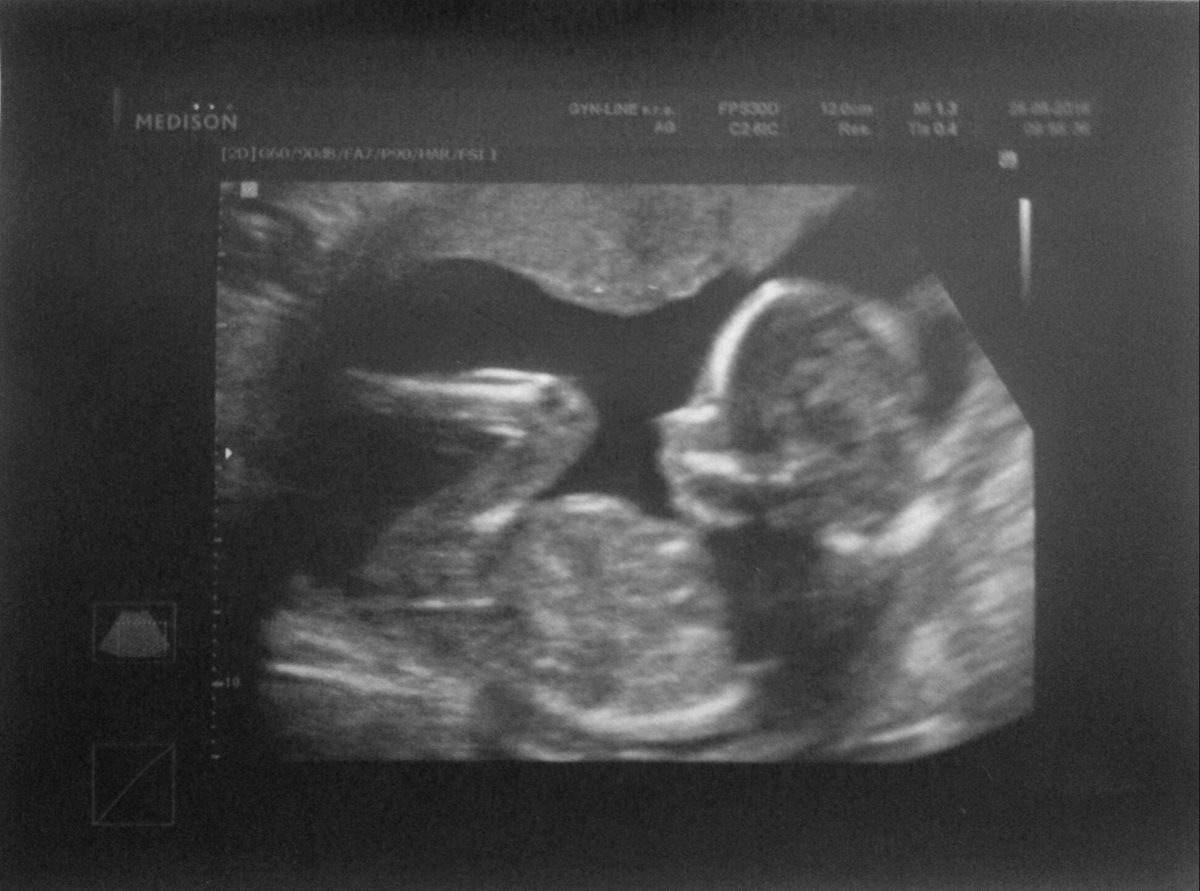

Fotografie (Je to chlapeček)

Fotografie (Je to chlapeček). Zdroj: archiv redakce